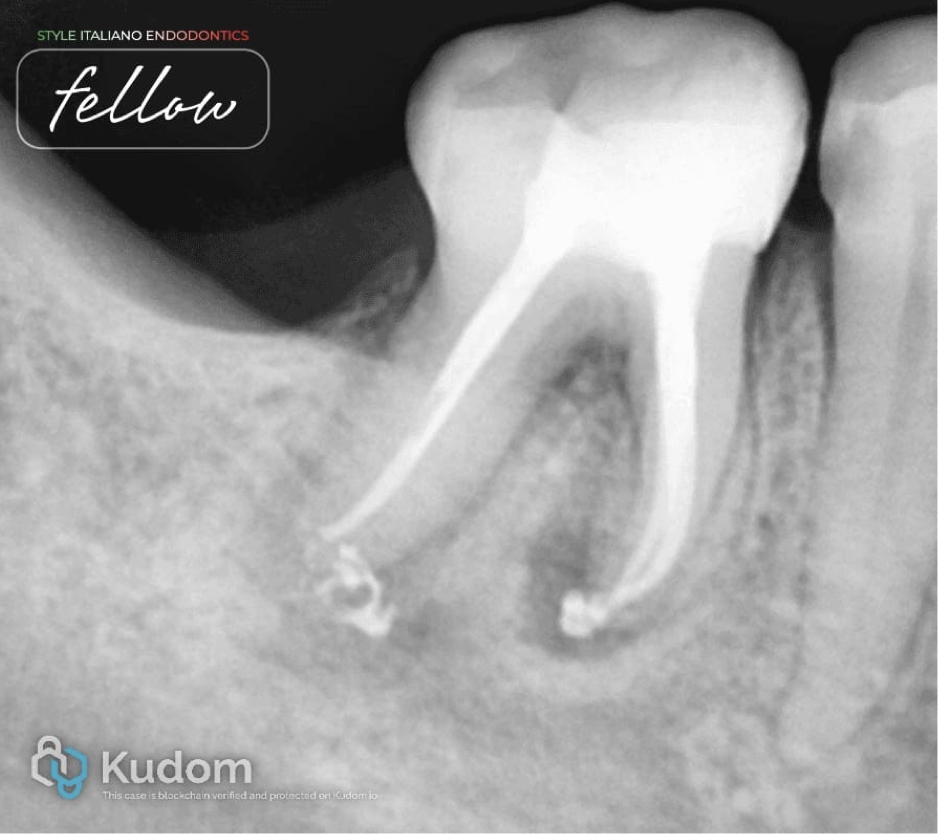

Fig. 4

After-obturation x-ray. Obturation was done with AH Plus sealer and the continuous wave of compaction method.